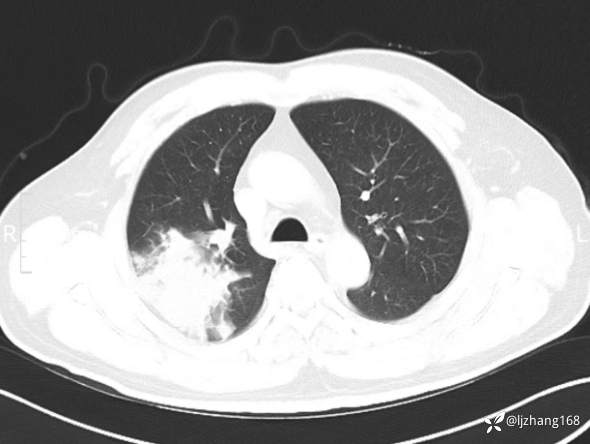

中年男患,右肺团片影,炎症0R肿瘤?

简要病史: 20+天前患者因受凉后出现阵发性咳嗽,咳少量白色粘痰,痰易咳出,伴活动后气短,伴纳差、乏力、全身酸痛,伴多汗,无痰中带血及咯血,无发热、畏寒及寒战,无潮热、盗汗,无夜间阵发性呼吸困难及端坐呼吸,无声嘶,无头晕、头痛,无黑矇、晕厥及意识障碍,无腹痛、呕血及黑便等不适,遂就诊于当地医院予以输液等治疗后未见明显好转(具体诊疗不详),现为进一步诊治就诊于我院门诊,以“右肺占位”收入我科。病来饮食欠佳,近期体重下降(具体不详)。既往糖尿病病史7+年,未规律监测血糖,血糖控制不佳。否认“高血压、冠心病及慢性肾脏病”等慢性疾病史。否认“肝炎、结核、伤寒”等传染病史。否认食物、药物过敏史。否认外伤、输血史,预防接种史不详。

辅助检查:糖化血红蛋白12.3%。肺炎支原体IgG、IgM、呼吸道合胞病毒均未见明显异常。胸部CT:右肺上叶阻塞性肺炎。